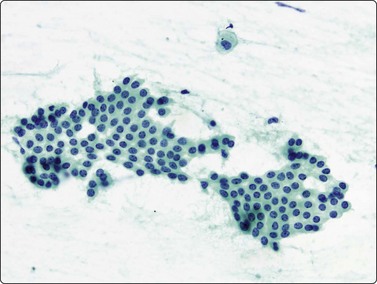

image image

Fig. 8.33 Carcinoid tumor

(A) Plexiform aggregate of small blood vessels with adherent tumor cells (Pap, LP); (B) Aggregate of small regular cells with stippled neuroendocrine nuclear chromatin pattern (Pap, HP).

image

Fig. 8.34 Carcinoid tumor

Dispersed regular tumor cells in company with small capillary blood vessels (H&E, HP).

In ‘classic’ carcinoid tumors, the FNB findings are often distinctive enough to permit diagnosis, with or without ancillary tests such as immunocytochemistry. In contrast, the atypical carcinoids that we have seen were more difficult to classify before resection. Nicholson et al. found similar problems in recognizing a proportion of their neuroendocrine carcinomas, including low- and high-grade tumors, and suggested that ‘attention to the presence of loose cell aggregates in a background of singly dispersed cells; feathery patterns created by tumor cells clinging to capillaries; rosette formations; delicate, granular cytoplasm; inconspicuous nucleoli; molding in high-grade tumors; and, most importantly, speckled or dusty chromatin patterns are useful in identifying neuroendocrine differentiation in cytologic specimens’.36